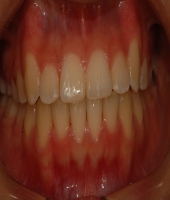

| ● 진료과목 : [치아교정] (교정)비발치 총생 치료

| ● 내용 : 심한 총생에서도 발치 없이 교정치료 |